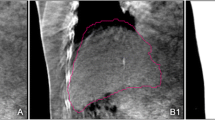

Immobilization, 4D-CT simulation, and treatment planning

Immobilization of the patients was achieved by a Vac-Lok cushion (MEDTEC, Orange City, IA, USA). Optimal abdominal compression was applied to all patients to achieve minimal while reproducible tumor motion. For each patient, 3 mm slice thickness 4D-CT images were acquired in helical mode on a Philips Brilliance Big Bore 16-slice CT scanner (Philips Medical Systems, Cleveland, OH, USA) and phase-sorted into ten bins of equal time share of the respiratory cycle. The TACE lipiodol was used as contrast medium in all 4D-CT scans to assist target delineation. Based on the lipiodol contrast on the 4D CT scan, the tumor trajectory and motion range was estimated for the three cardinal directions: x, y and z corresponding to the left–right (LR), craniocaudal (CC), and anteroposterior (AP) directions, respectively. Next, the time-weighted mean tumor position (MidP) and its corresponding time-percentage were calculated as described in our previous study [13], and 1 of the initial 10 4D-CT phases that was closest to this midventilation (MidV) time percentage was selected for tumor delineation, treatment planning, and as the reference images for image guidance. Note that the MidV alternative of MidP ignored the fact that some tumors exhibited hystersis over their breathing trajectories. Therefore, a small systematic error would be introduced. The mean tumor vector error of MidV relative to the MidP approach has been estimated at 1.0 ± 0.5 mm, which was within image resolution [14].

Quantitative assessment of the lipiodol/diaphragm position on 4D-CBCT data

Only lipiodol retention that was classified as homogeneous accumulation and partial defect [16] in both the simulation 4D-CT and treatment verification 4D-CBCT scans was considered as an acceptable surrogate for inclusion in the analysis. A total of 186 4D-CBCT scans were analyzed, with 4–7 scans per patient including the first and last scans and other 2–5 scans in between. The interfractional changes of absolute tumor position (i.e., treatment setup) were analyzed separately for IG correction protocols using the centroid positions of the lipiodol and liver contours at MidP. The interfractional change of absolute lipiodol/diaphragm position was obtained from the result of 4D registration of each scan as the difference of lipiodol/diaphragm at MidP on the 4D-CBCT compared with the lipiodol at MidV on the planning 4D-CT. Pearson’s correlation coefficient (r) was used to assess the relationship of the interfractional changes of the absolute lipiodol and diaphragm positions.